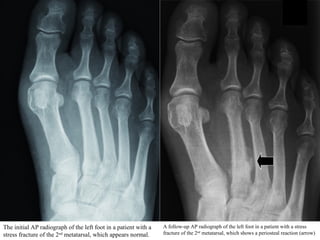

The initial AP radiograph of the left foot in a patient with a

stress fracture of the 2nd

metatarsal, which appears normal.

A follow-up AP radiograph of the left foot in a patient with a stress

fracture of the 2nd

metatarsal, which shows a periosteal reaction (arrow)